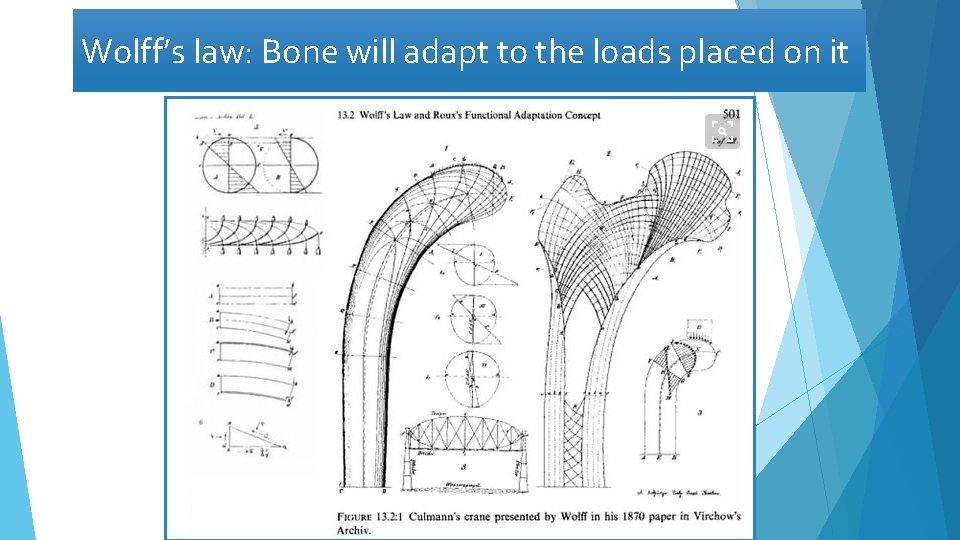

Wolff’s law: Bone will adapt to the loads placed on it